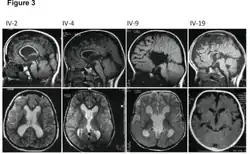

Left-sided hemimegalencephaly in a person with neurofibromatosis[8]

Hemimegalencephaly is an extremely rare form of macrocephaly and is characterized by uneven development of brain hemispheres (one half of the brain is larger than the other).[9] It can present by itself or in association with phakomatosis or hemigigantism. Additionally, hemimegalencephaly will frequently cause severe epilepsy, focal neuro-logical deficits, macrocrania, and mild to severe intellectual disability.[10]